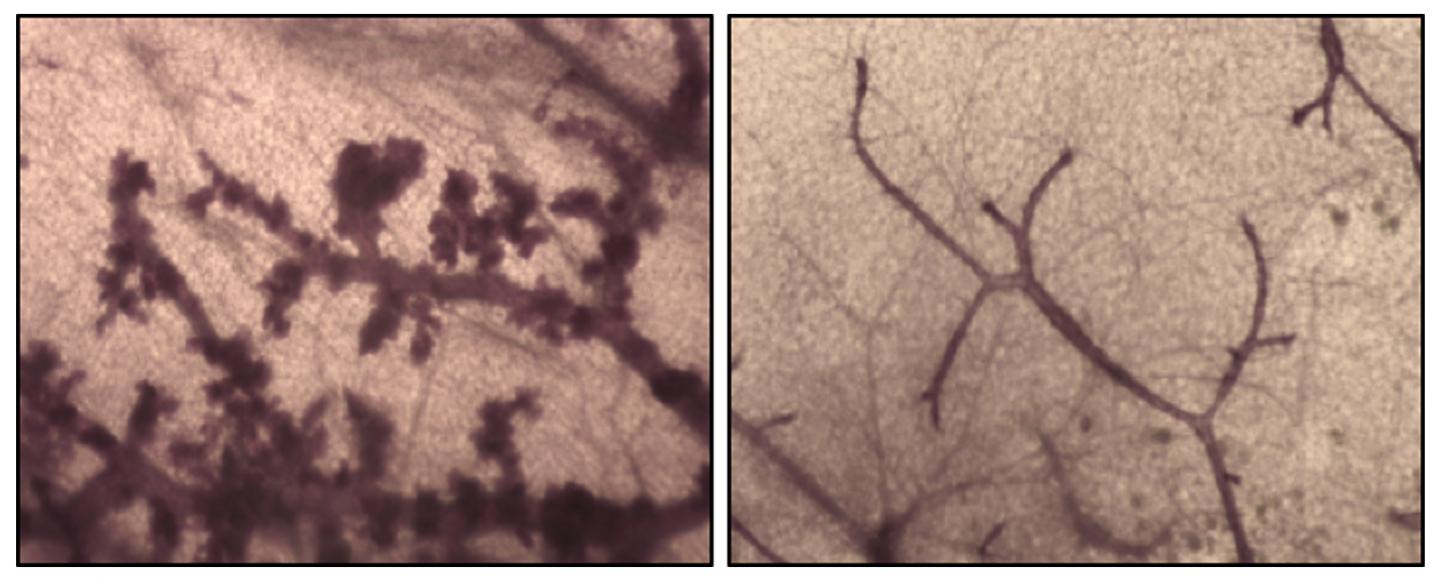

Dr. Penninger's results showed that inactivation of RANK markedly delayed and in some cases even prevented the development of breast cancer in mice with mutated BRCA1. The loss of RANK also impaired the progression of breast tumors to high-grade malignancies. These effects were observed both when RANK was inactivated genetically and when mice received preventive pharmacological RANKL inhibitors.

Dr. Penninger has documented that RANK/RANKL are highly expressed in pre-malignant lesions and breast cancer in women with BRCA mutations, and that common variants of RANK are associated with increased breast cancer risk among these women. Future experiments, especially carefully designed clinical trials, will be needed to assess whether RANKL inhibitors offer an advantage over current prevention techniques like Tamoxifen or oophorectomy. However, these findings raise the exciting possibility that inhibition of RANKL, for which there is already a drug that has a good safety record and is approved by the Food and Drug Administration, could offer a novel, targeted approach for breast cancer prevention in women with BRCA1 mutations.